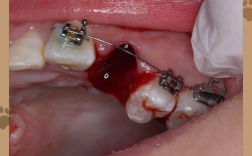

- 拔牙: 在正畸开始前或开始后不久,由口腔外科医生或正畸医生在局部麻醉下完成拔牙,拔牙位置通常选择在后续移动中能被其他牙齿占据或关闭的位置。